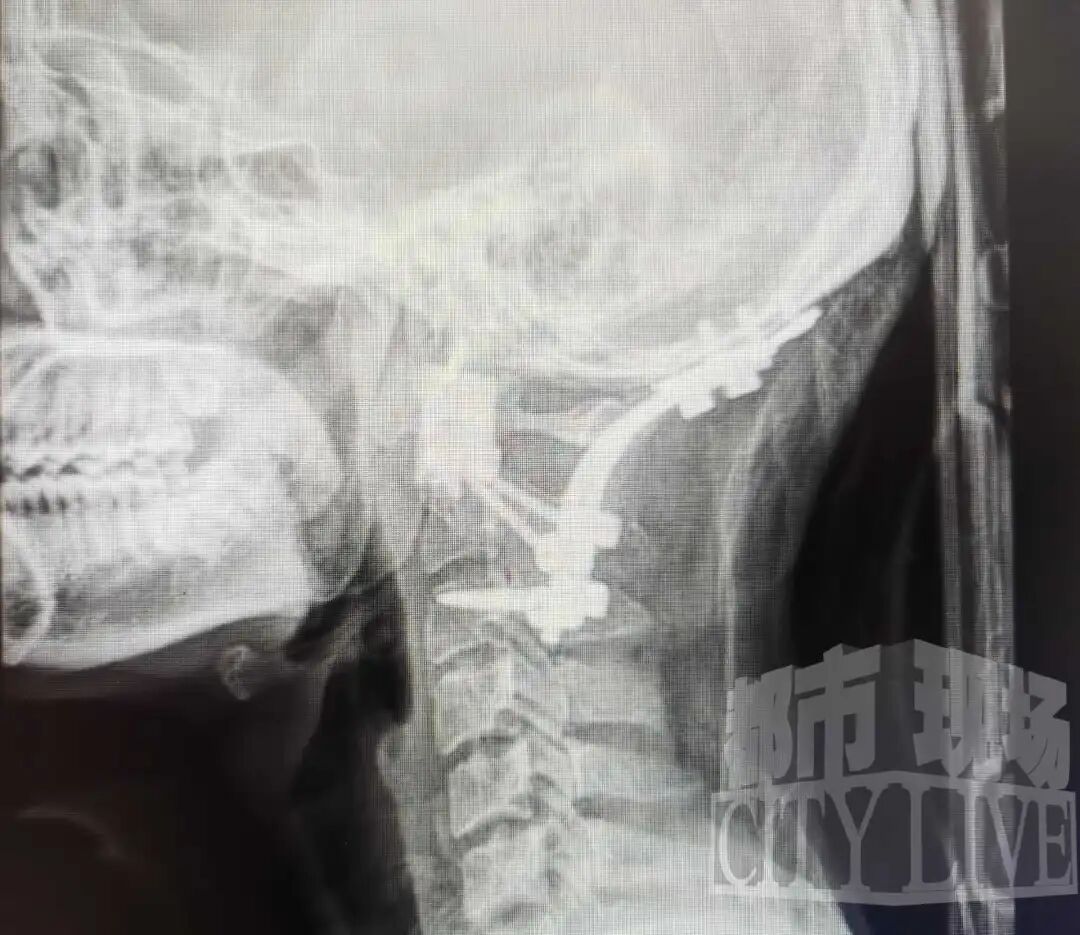

南昌大学一附院骨科医院副院长、主任医师姚浩群告诉《都市现场》记者,团队通过3D打印模型清晰展示了肿瘤的复杂情况:它从第一颈椎长出,缠绕着关键的椎动脉向前生长至咽后壁,紧邻食道、气道和重要脊髓神经,严重破坏骨质。若肿瘤继续发展,无论向后压迫延髓导致呼吸衰竭,还是向前生长引发气道梗阻,都将危及生命。

寰枢椎手术本就是脊柱外科“皇冠上的明珠”,肿瘤切除更是难上加难。为确保万无一失,医院集结了麻醉、影像、康复等多学科精英,还利用3D打印技术为他“量身定制”了人工椎体。11月26日,手术正式开始,仅用四个小时,病灶被完整摘除。

姚浩群医生介绍,手术的关键在于小心分离被肿瘤包裹的椎动脉,之后切断与正常骨质的连接,将肿瘤完整取出,并利用3D打印的人工椎体进行精准重建,完美恢复了该部位的稳定性。